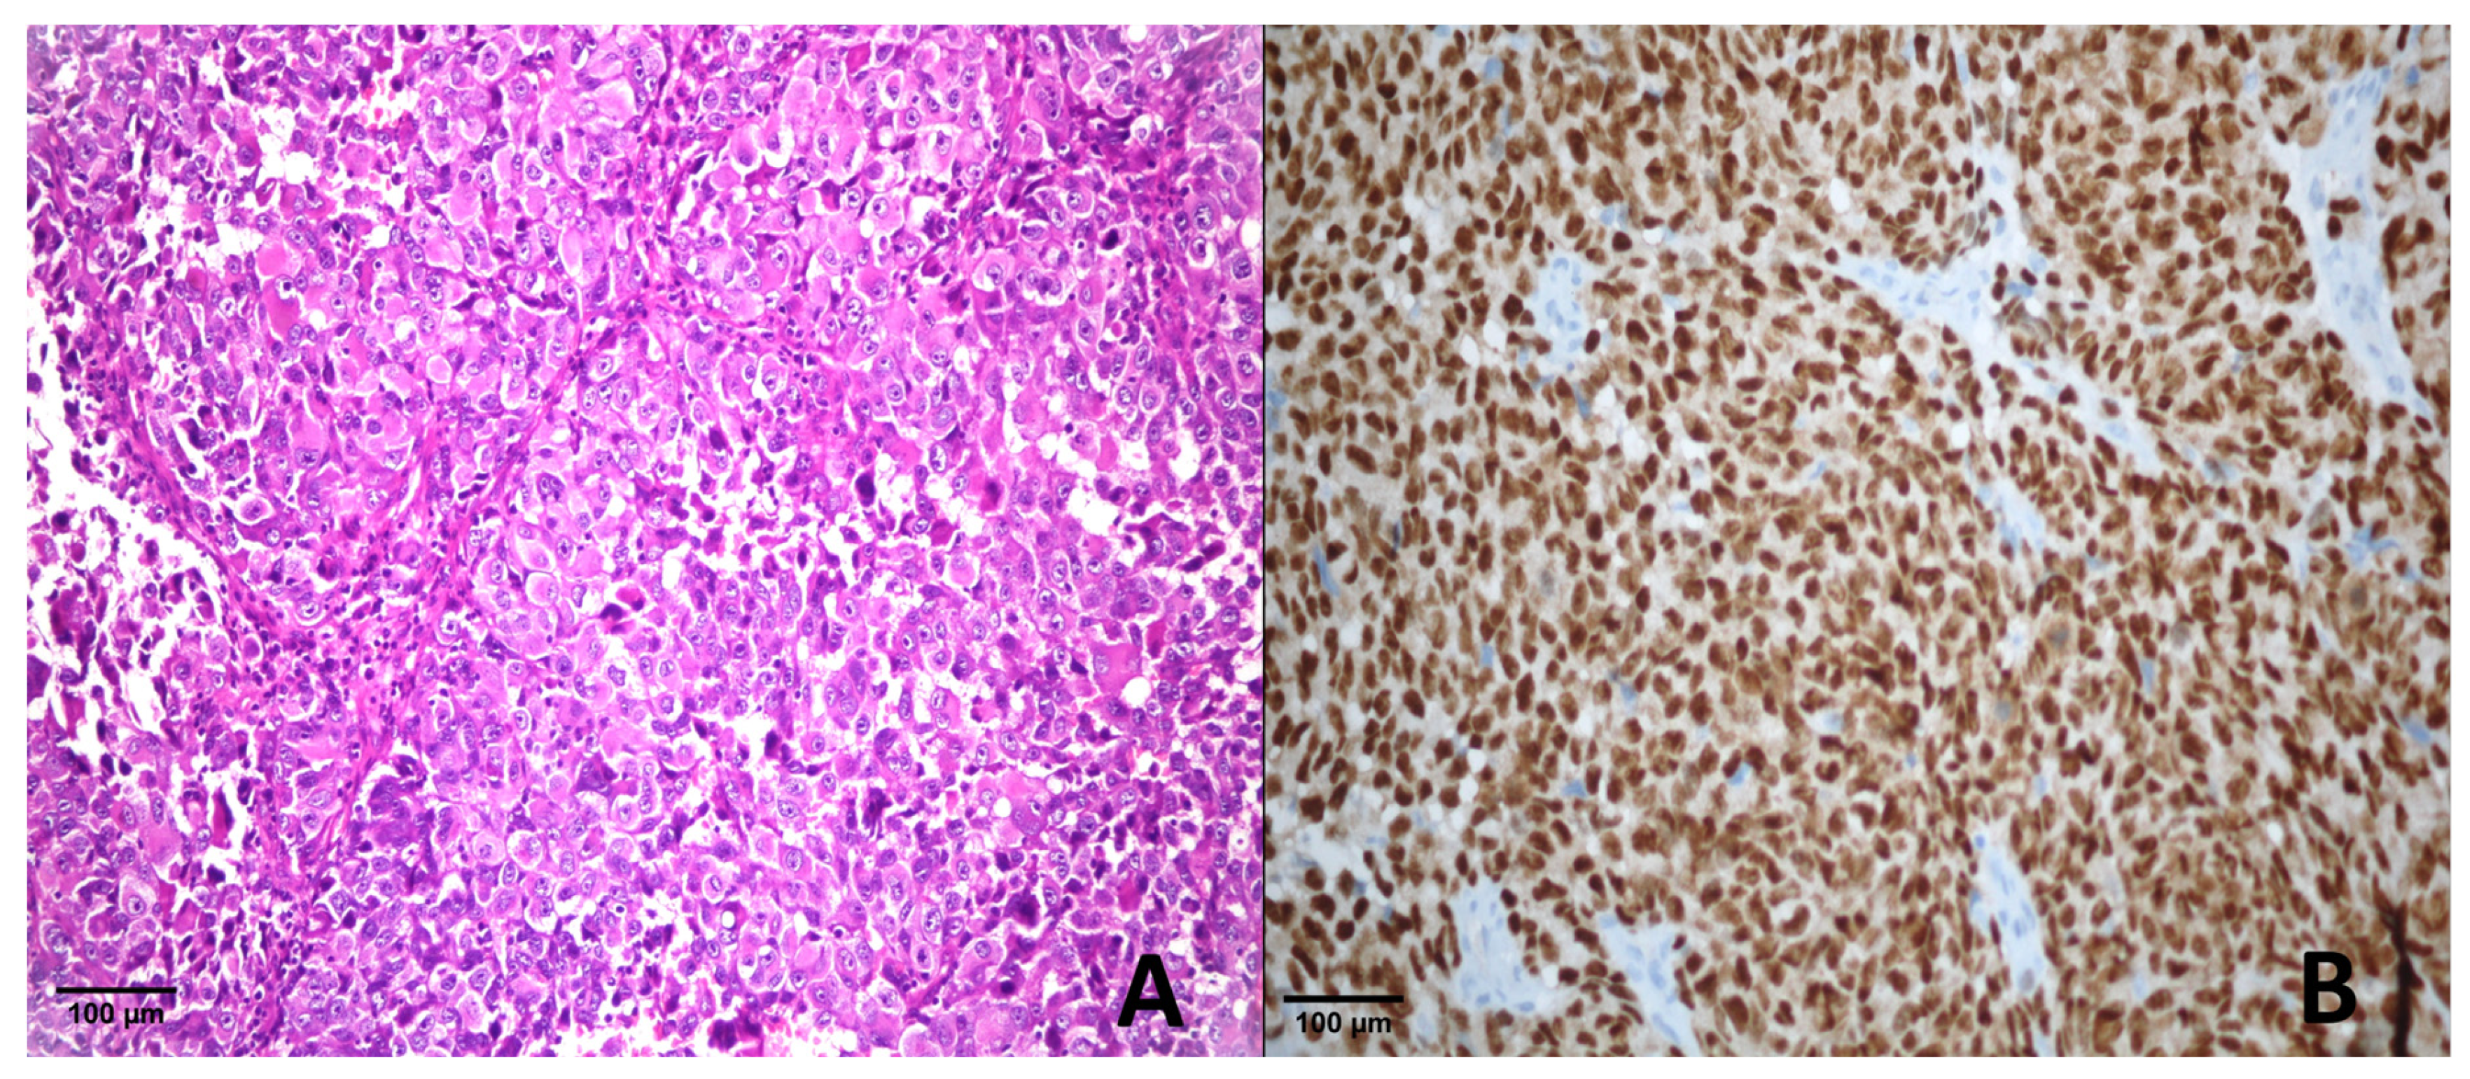

3.2. Immunohistochemical Results

3.2.1. Comparison of PRAME Cut-Off Groups in Melanoma and Benign Lesions